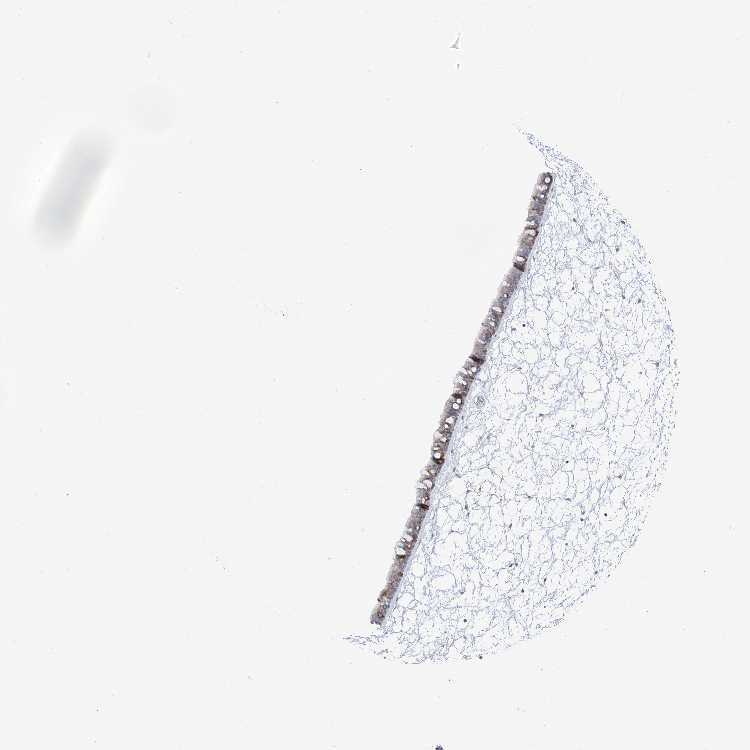

NASOPHARYNX - Antibody stainingi

Antibody staining in the annotated cell types in the current human tissue is reported as not detected, low, medium, or high, based on conventional immunohistochemistry profiling in selected tissues. This score is based on the combination of the staining intensity and fraction of stained cells.

Each image is clickable and will lead to virtual microscopy that enables deeper exploration of all samples and also displays staining intensity scores, fraction scores and subcellular localization as well as patient and tissue information for each sample.

Antibody HPA035639

Respiratory epithelial cells Low